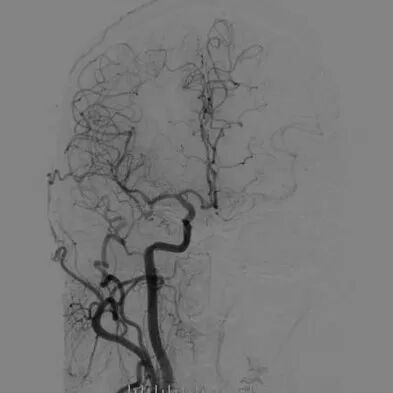

心脑联合造影

-- 右侧颈内起始部中度狭窄,经前交通向左侧代偿

-- 左侧颈内起始部重度狭窄

-- 右侧椎动脉起始部中度狭窄

-- 左侧椎基底动脉无明显异常

-- 冠脉多发狭窄